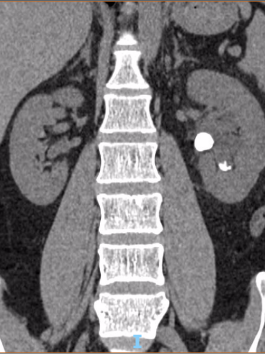

吴先生是一名办公室职员,近期总被间断性腰痛困扰,起初他以为是腰椎间盘突出,并未在意,直到腰痛加剧才到荆州市第一人民医院就诊。CT检查结果让他心头一紧——左侧肾脏竟藏着一颗直径2公分的结石,且已引发肾脏积液。

手术在医院日间手术病房顺利开展,吴先生术后无需留置肾脏引流管,身体状态恢复迅速,不到24小时就达到出院标准。出院时,他看着清晰的术后影像,连连感慨医疗技术的神奇与高效。

术前

术后